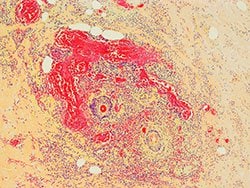

In the more common form of MODS, the lungs are the predominant, and often the only, organ system affected until very late in the disease. Patients with this form of MODS most often present with a primary pulmonary disorder (eg, pneumonia, aspiration, lung contusion, near-drowning, chronic obstructive pulmonary disease exacerbation, hemorrhage, or pulmonary embolism). In the second, less common, form of MODS, the presentation is quite different. Patients affected by this form often have an inciting source of sepsis in organs other than the lung; the most common sources are intra-abdominal sepsis, extensive blood loss, pancreatitis, and vascular catastrophes.